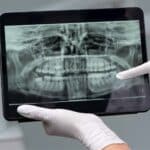

October 2, 2025Radiografia panoramică, cunoscută și sub denumirea de ortopantomografie sau pe scurt OPG, este una dintre cele mai folosite investigații imagistice în stomatologie. Aceasta oferă o imagine completă a dinților, maxilarului, mandibulei, articulațiilor temporo-mandibulare și sinusurilor maxilare. Prin vizualizarea întregii structuri dento-maxilare într-o singură imagine, medicul poate stabili un diagnostic precis și poate planifica tratamente eficiente.